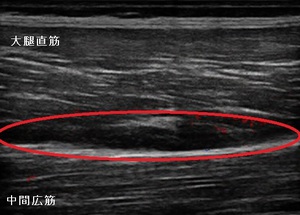

左大腿部 超音波長軸像 右同部 健(正常)側

圧痛と熱感が著明で、超音波観察を行ったところ、左大腿四頭筋のうち大腿直筋の近位で中間広筋との境界部で

肉離れを起こしている様子が認められました。(左上画像の丸の囲み)